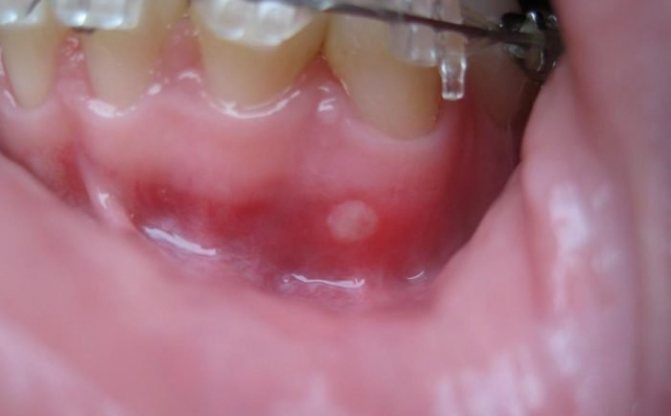

- Эпителиальная гиперплазия — небольшие образования в виде сосочков, чаще всего образующиеся по бокам языка;

Эпителиальная гиперплазия

- Простая (вульгарная) папиллома появляется на небе и имеет форму приплюснутой шишки;

Вульгарная папиллома

- Наросты на десне чаще всего представлены в виде плоской папилломы;

Плоские папилломы